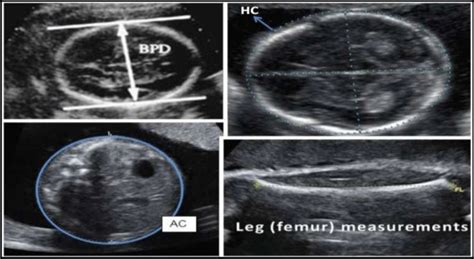

• BPD (Biparietal Diameter): This measures the diameter of your baby’s head from one side to the other. Think of it like measuring the widest part of their head. It’s one of the most common measurements and helps estimate how far along your pregnancy is and how well the head is developing.

• HC (Head Circumference): This measures the circumference, or the distance around, your baby’s head. It’s a key indicator of head size and brain development. Often, the HC measurement is used together with the BPD measurement for a more accurate assessment.

• AC (Abdominal Circumference): This measures the circumference of your baby’s abdomen. This measurement helps assess the baby’s weight and overall growth. It’s particularly useful in detecting potential issues like growth restriction or, on the other hand, the baby is too big for the gestational age.

• FL (Femur Length): This measures the length of your baby’s femur, which is the thigh bone. The FL can be used to estimate your baby’s gestational age and size, just like the other measurements. It’s an important measurement because it can provide clues about skeletal development.